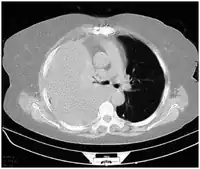

Hemothoraces are most commonly detected using a chest X-ray, although ultrasound is sometimes used in an emergency setting.[22] It can be suspected in any person with any form of chest trauma.[6] However, plain X-rays may miss smaller hemothoraces while other imaging modalities such as computed tomography (CT), or magnetic resonance imaging may be more sensitive.[22] In cases where the nature of an effusion is in doubt, a sample of fluid can be aspirated and analysed in a procedure called thoracentesis.[8] Physical examination is used initially. Auscultation has been reported to have an accuracy of nearly 100% in diagnosing hemopneumothorax.[3]

Computed tomography (CT or CAT) scans may be useful for diagnosing retained hemothorax as this form of imaging can detect much smaller amounts of fluid than a plain chest X-ray. However, CT is less used as a primary means of diagnosis within the trauma setting, as these scans require a critically ill person to be transported to a scanner, are slower, and require the subject to remain supine.[23][26]